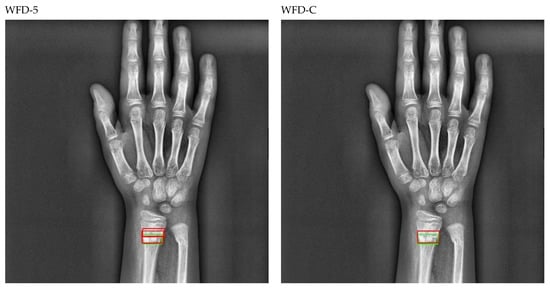

The bounding box outputs achieved from the fracture detection performed with the PAA model with the best AP50 score are displayed in Figure 17 for right/left hand as a sample in the dataset, and the precision-recall graph is provided in Figure 18.

Figure 17.

Sample of left/right wrist fracture results [ground-truth bounding box (green), predicted bounding box (red)] for PAA (Best score of 20 models).

Figure 18.

Precision-recall curve of PAA (best score of 20 models).